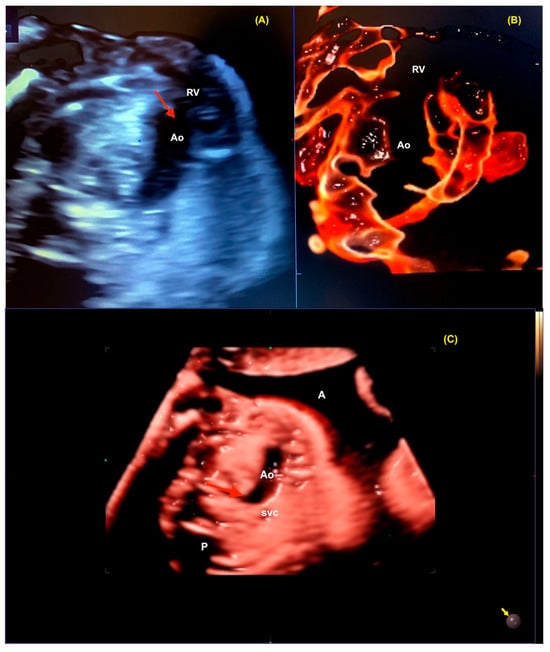

5. Realistic Vue, Crystal Vue, and LumiFlow

Realistic Vue, Crystal Vue, and LumiFlow (Samsung Healthcare, Gangwon, South Korea) provide more detailed and realistic images of the fetus with instant processing, and Crystal Vue improves the visualization of internal and external structures in a single rendered image (Figure 9 and Figure 10 and Video S6). LumiFlow is a post-processing and shading technique used to better assess the fetal micro- and macrovasculature of the fetus. This technology can be added to existing Doppler images, such as color/power, to simulate a 3D pace view of the fetal vasculature. With LumiFlow, the center of the vessel is displayed in a slightly lighter color due to its faster velocity, with a darker border around the vessels where blood velocities are slower (Figure 11) [38,39].

Figure 11.

The aortic arch as assessed by LumiFlow at 14 weeks gestation. RA: right atrium; Ao: aorta; svc: superior vena cava; ivc: inferior vena cava.